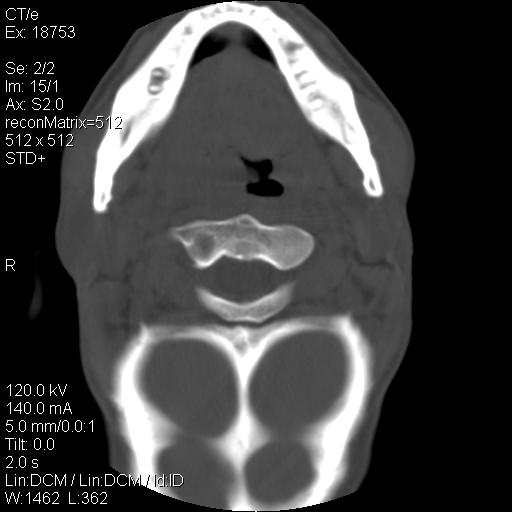

标题: CT21693:男 58岁 右侧咽部疼她2天余 PE:右侧扁桃体肿大 压痛 [打印本页]

标题: CT21693:男 58岁 右侧咽部疼她2天余 PE:右侧扁桃体肿大 压痛

喉部新生物,喉癌可能大,建议喉镜取组织活检。

右化脓性扁桃体炎症伴咽后壁脓肿形成.